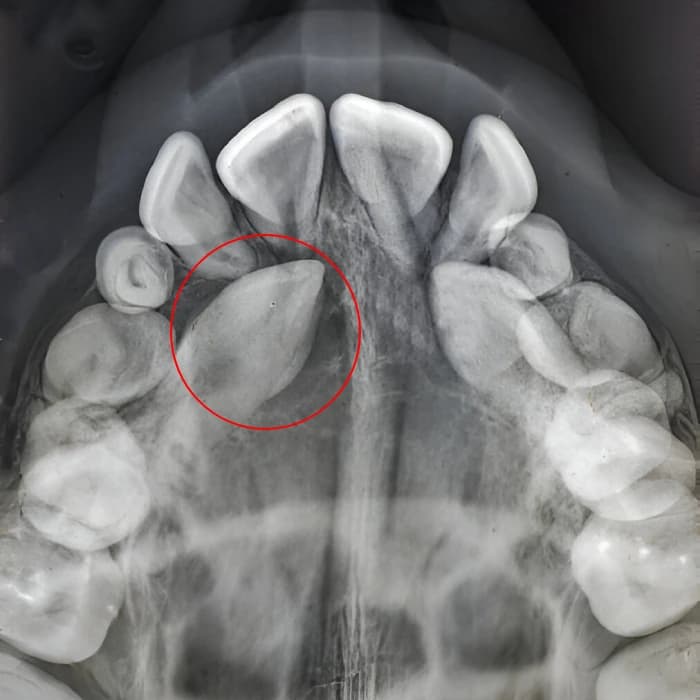

گاهی دندان نیش نهفته به صورت افقی در استخوان قرار میگیرد و این حالت یکی از پیچیدهترین فرمهای نهفتگی است. در چنین شرایطی، دندانپزشک باید استخوان بیشتری را کنار بزند تا به دندان دسترسی پیدا کند. گاهی این دندان به دلیل موقعیت نامناسب قابل نگهداری نیست و به طور کامل خارج میشود. این نوع جراحی نیازمند تخصص و تجهیزات پیشرفته است.

دندان نیش نهفته در فک پایین کمتر از فک بالا دیده میشود اما در صورت بروز نیازمند جراحی دقیقتری است. موقعیت استخوانی و ریشههای قویتر دندان نیش فک پایین میتواند جراحی را کمی پیچیدهتر کند. دندانپزشک با بررسی تصاویر رادیوگرافی بهترین روش را برای دسترسی به دندان انتخاب میکند. این عمل ممکن است طولانیتر از جراحی فک بالا باشد.